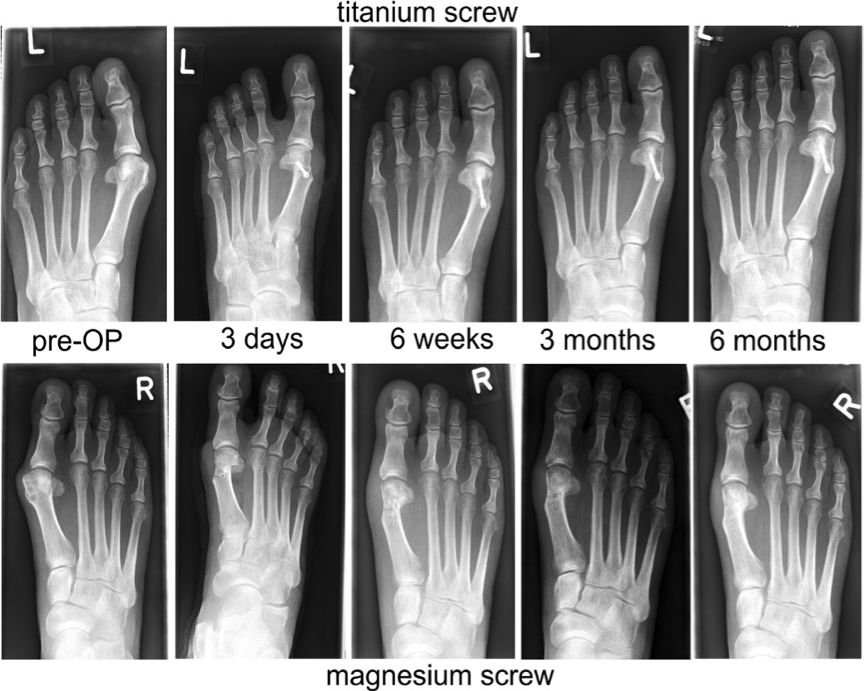

早在1907年,Lambotte就使用铁丝环扎术和一块带有六个钢螺丝的镁板来固定骨折的小腿,但是由于镁和铁接触后发生电化学反应,加速了镁的腐蚀,术后一天即观察到了大量的皮下气腔,并伴有局部有肿胀和疼痛。因此在排除了镁和其他金属混用后,Lambotte与其助手用镁钉治愈了4例儿童肱骨髁骨折,除发现气泡产生外,没有其它不良反应发生。 Jean Verbrugge在接下来的几年里,采用镁及其合金(AZ63和Mg-8wt.%Al)进行了25例骨折治疗的临床实验,如图2所示。由于镁在植入后的快速腐蚀降解,镁板和镁钉固定系统植入三周后,骨折线即消失不见。除此之外,有病人反映,植入部位会有暂时的麻木感觉,但没有组织感染迹象或不良反应发生。在这些病例中,因植入尺寸以及位置不同,镁在人体内在三个星期到一年最终吸收。 McBride进行的临床应用探索,发现镁可以加速治疗初期结缔组织的早期增殖和愈合组织的增生。1940年,Maier使用了由梭形镁片制成的针治疗肱骨骨折,并且在接下来的14年获得良好的恢复。 近年来,随着金属材料技术的发展,镁合金的力学性能和耐蚀性能均得到大幅改善。生物可降解金属新概念的提出,使镁基金属的医学应用研究又重新获得重视,针对可降解镁基金属材料在骨科植入物产品中的应用进行了大量的体内外研究。 在2005年,Witte等研究了铸态AZ31、AZ91、LAE442以及WE43四种工业用镁合金在豚鼠股骨内的植入行为。研究结果表明,在植入1周后所有实验组中均在皮下发现了H2气囊,但这些气囊在2-3周后自行消失,没有对豚鼠产生不良影响。同时,这四种镁合金表面在降解的过程中均形成了一层与周围骨组织直接接触的含Ca以及P的矿物层。与PLA对照组相比,在植入6周、18周之后,镁合金的植入显著的增加了骨膜处和骨内膜处新骨生成量。 2007年Duygulu等将AZ31镁合金螺钉植入羊的髋骨,在植入3个月后,螺钉发生了明显的降解,降解的部分被新生骨所取代。 近几年先后有纯镁及镁合金材料的临床植入研究报道。2013年,Windhagen等进行了MgYREZr合金空心螺钉进行脚拇指外翻手术后固定的临床研究工作。MgYREZr合金螺钉植入的6个月内,在植入部位没有观察到排异反应、骨溶解以及炎症反应,同时也未见跖趾关节强直现象。影像学检测表明,植入物部位没有发生缺血性坏死以及气体聚集。植入6个月后,MgYREZr合金螺钉未全部降解,骨组织已经完全愈合。 通过前期的基础研究和临床试验研究发现,可降解镁基金属具有良好的生物相容性和骨诱导性,同时由于材料科学的进步,其降解速率也能控制在合理的范围内,虽然由于其力学性能的不足,目前在临床上的应用范围具有一定的局限性,但其良好疗效已经预示着可降解镁作为骨科植入物具有广阔的发展前景。